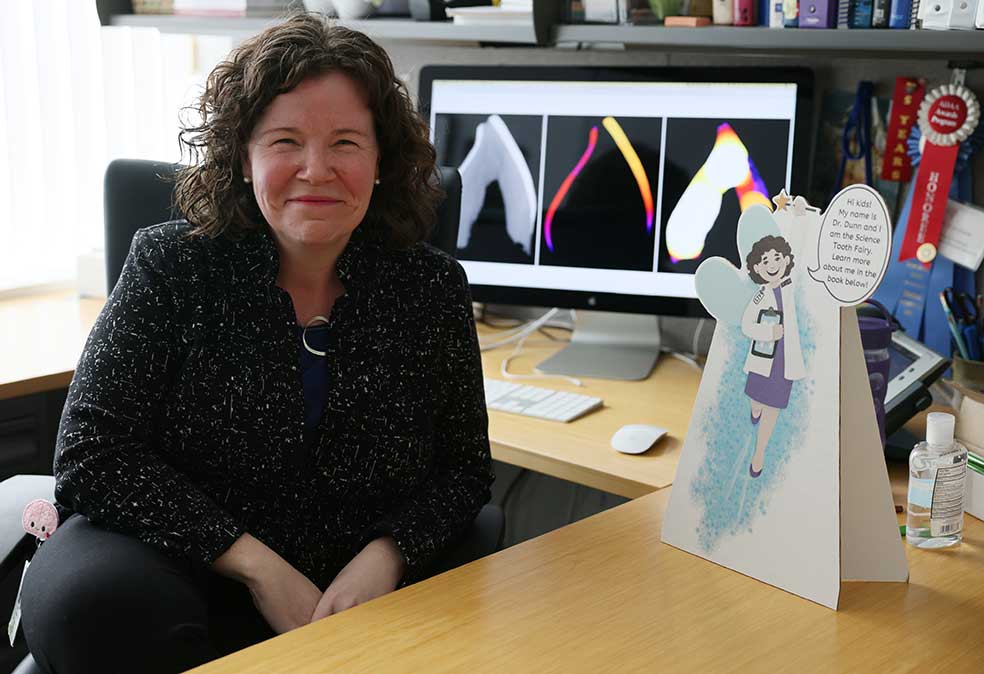

Ahora, los científicos creen que no hay por qué restringir esta información a lo ocurrido hace miles de años. Erin Dunn, epidemióloga social y psiquiátrica en el Hospital General de Massachusetts, se ha propuesto comprobar si los dientes de leche caídos de forma natural pueden funcionar como un 'archivo' de hechos ocurridos en nuestra tierna infancia. O incluso antes.

Si la violencia u otro trauma o dificultad (léase guerra o desastre natural) ha aparecido en la infancia, durante el desarrollo de la estructura cerebral, es fácil que los niños crezcan con problemas cognitivos o emocionales o una mayor propensión a padecer cáncer o enfermedades coronarias. Para la investigadora Erin Dunn resulta importante contar con un indicador objetivo que muestre problemas psiquiátricos padecidos en la infancia. Y lo ha encontrado en los dientes que decenas de voluntarios le envían. Son analizados por rayos X y tomografía axial antes de cortarlos en finas 'rebanadas' que permiten analizar los anillos de esmalte. Y buscar huellas de eventos traumáticos.